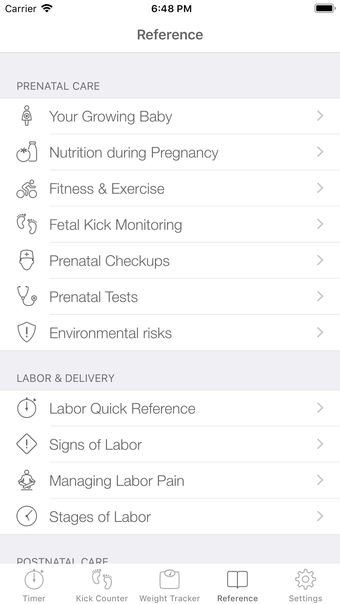

이 어플리케이션은 조기 분만을 겪는 여성들이 분만 과정을 지속적으로 추적할 필요가 있는 경우에 디자인되었습니다. 기능성을 희생하지 않고 사용자 친화적인 어플리케이션을 만들고자 했습니다.